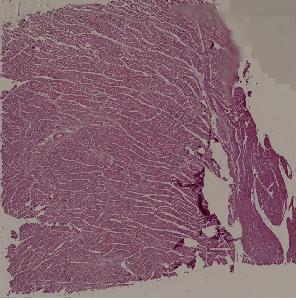

27. Squamous cell carcinoma of the esophagus